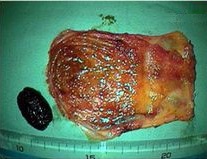

手術標本